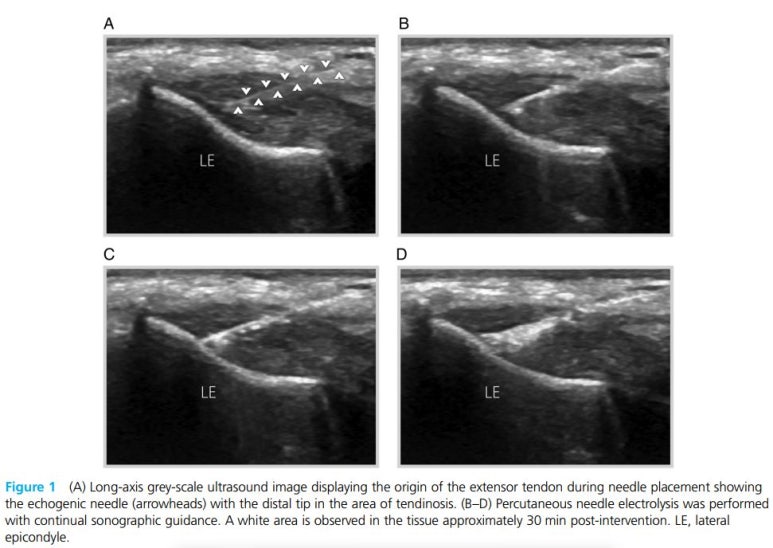

즉, 침치료, 전기침 치료, 드라이니들링, PRP주사, 고주파치료, 경피바늘 건 절제술 등에 대한 관심이 높아지고 있는 상황입니다.** > 경혈 초음파 유도하 침 전기 치료 Percutaneous needle electrolysis(PNE)는 ## 경혈 초음파 유도하 침 치료 후 전류를 통하게 하는 치료법**으로 한의 비수술 치료입니다.

초음파를 통해 실시간으로 혈 자리를 찾고, 해당부위에 침 치료를 한 뒤 세포의 활동과 회복을 증가시키는 것입니다.

전기 침치료는 대략 3초당 4-6mA의 강도로 약 3회 정도 자극을 주었고, 공통 신전근의 깊은 표면을 타겟으로 시술하였습니다.